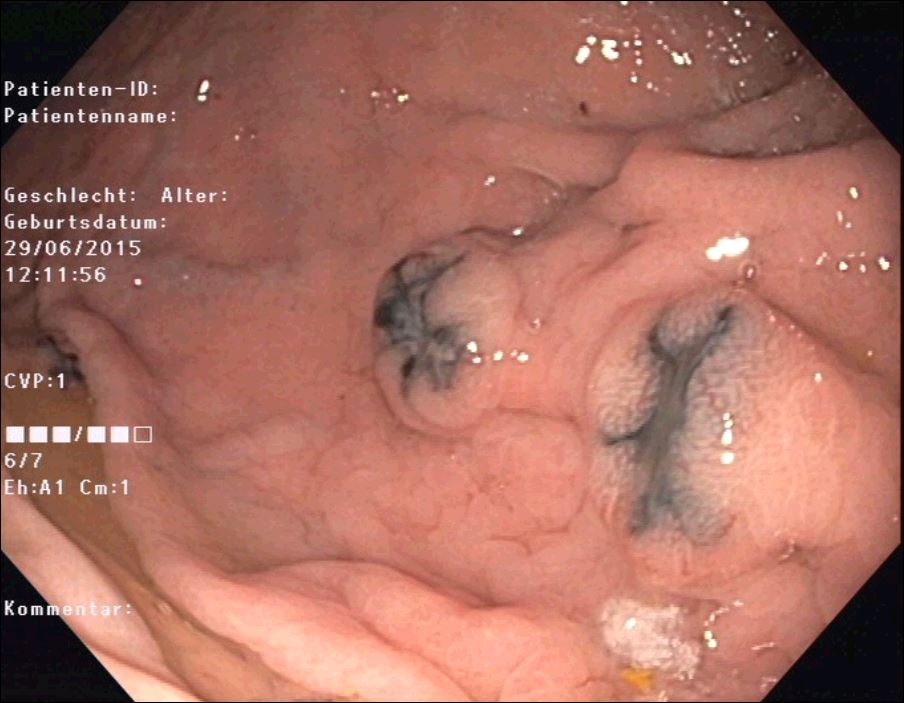

Unfortunately, the following endoscopy revealed multiple metastases in the stomach, duodenum and colon (Fig. 4-6) that endoscopically and histologically confirmed as metastasis of a malignant melanoma.

Figure 4: Polypoid melanoma metastasis in the duodenum. Note central depression as a sign of malignancy. The neighboring mucosa is completely preserved as well as the neighboring gallbladder wall in figure 1-3.

Figure 5: Polypoid melanoma metastasis in the stomach. Typical black color.